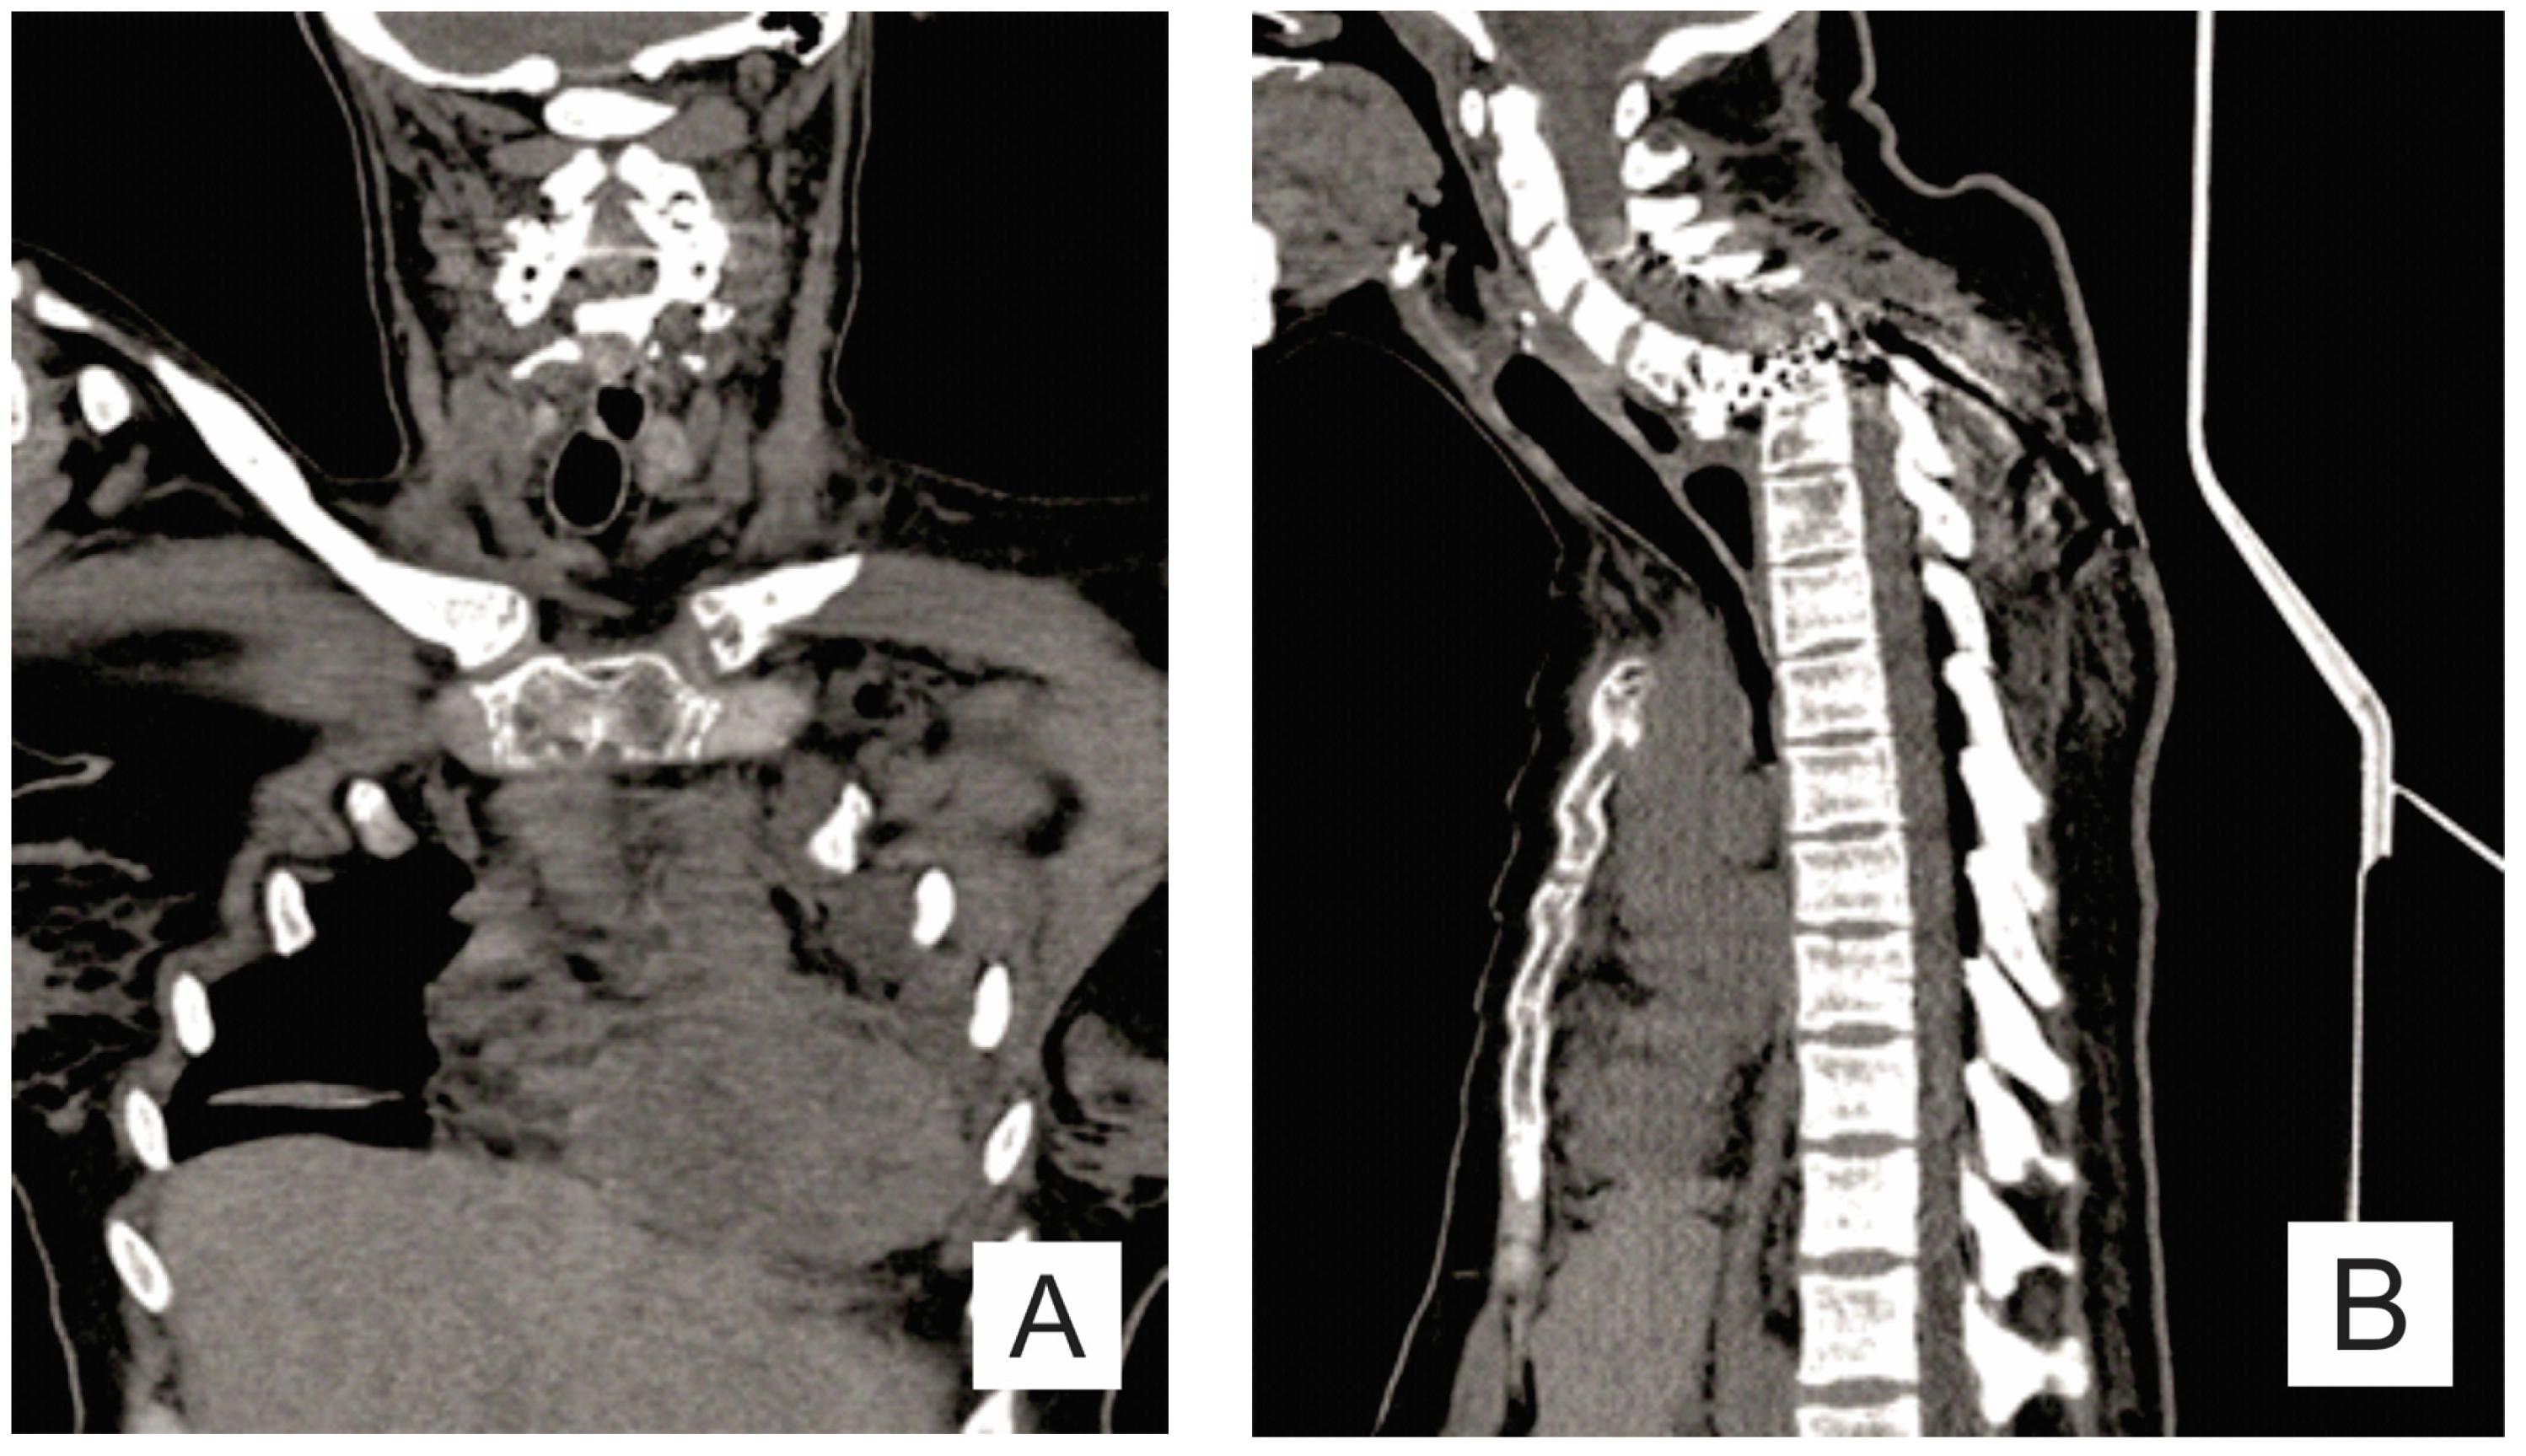

- Chung, C.; Yu, J.S.; Resnick, D.; Vaughan, L.M.; Haghighi, P. Gorham syndrome of the thorax and cervical spine: CT and MRI findings. Skeletal Radiol. 1997, 26, 55–59. [Google Scholar] [CrossRef] [PubMed]

| Month I | C7 corpectomy and reconstruction with autologous graft from the iliac crest, macroscopic resection of the posterior arches C7-T1 and fixation with C4-C5-T3-T4 cervico-thoracic hybrid system |

| Month III | Ablation of osteosynthesis material and bone graft and T1 corpectomy, reconstruction with C6-T1 mesh fixed with proximal and distal screw |

| Month IX | Ablation of damaged osteosynthesis material mesh C6-T1, ablation of thoracic screws, and introduction of bilateral T3, T4, and T5 screws |